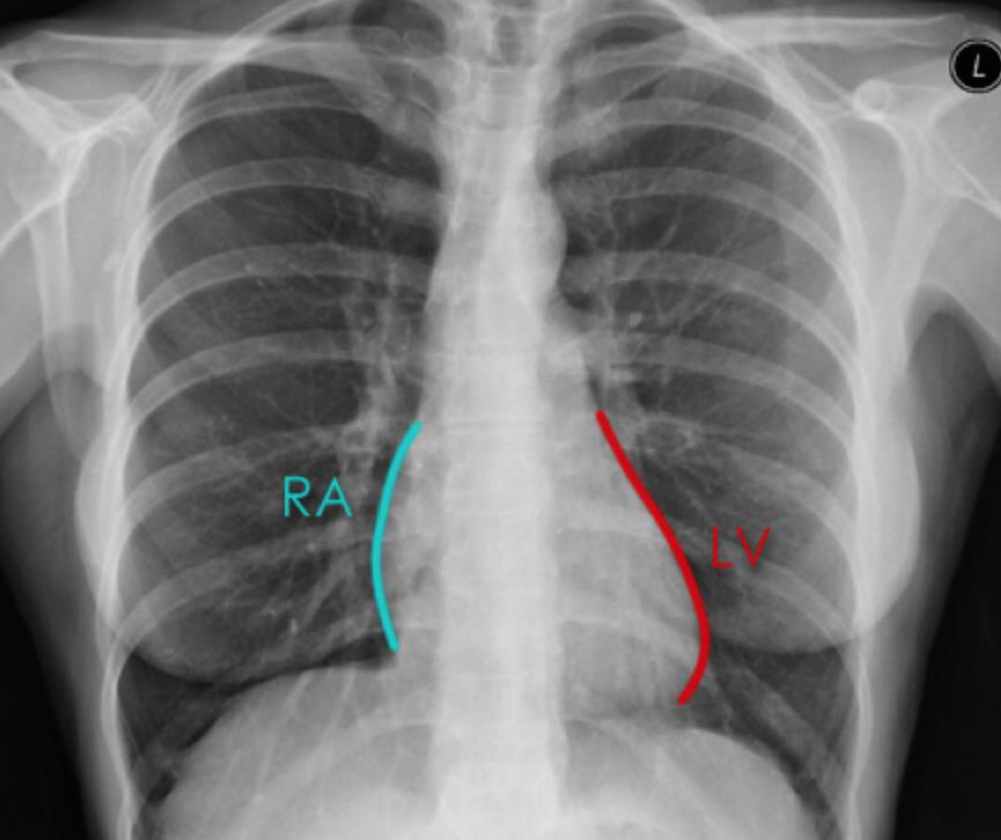

What borders of the heart should you see on a chest x ray?

Atrial enlargement carina splays